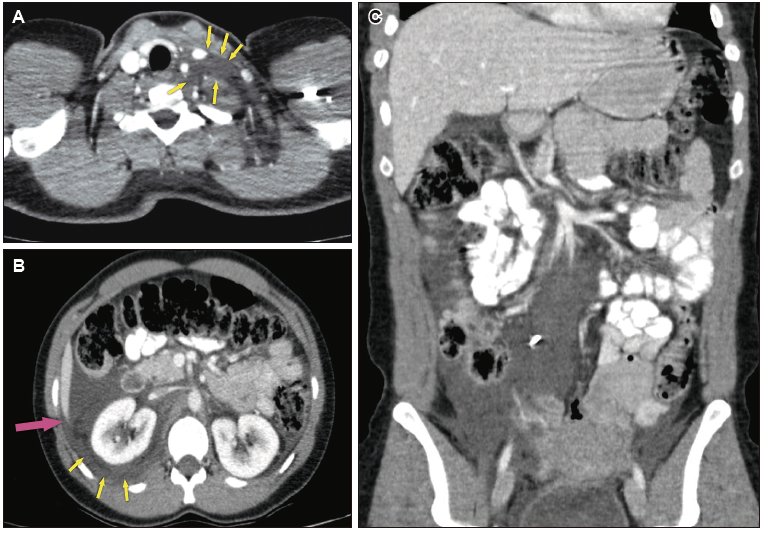

Se realiza una ecografía abdominal que evidencia la presencia de líquido libre. En la TC de tórax y abdomen con contraste oral y endovenoso realizada a continuación se observa un linfocele supraclavicular izquierdo (Figura A), una colección hipodensa perirrenal derecha extendida al espacio periaórtico y presacro y líquido libre perianexial, en las fosas ilíacas y en el espacio de Morrison (Figuras B y C).

Figura. A) Tomografía computada de tórax, corte axial. Linfocele supraclavicular izquierdo. B) Tomografía computada de abdomen, corte axial. Colección hipodensa perirrenal derecha extendida a espacio periaórtico. C) Tomografía computada de abdomen, corte coronal. Líquido libre en cavidad peritoneal (espacio de Morrison y fosas ilíacas)